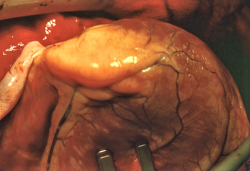

Equipo del Dr. Bartley P. Griffith durante la operación del xenotrasplante. Tras dos meses viviendo gracias al corazón de un cerdo, David Bennett de 57 años, falleció por causa aún no determinada. La comunidad científica mundial acogió este primer xenotrasplante con la lógica incertidumbre y respeto, debido al importante bagaje científico

Han pasado 55 años desde el primer trasplante de corazón humano, llevado a cabo por Christiaan Barnard, en Ciudad del Cabo (Sudáfrica), cuando el pasado viernes 7 de enero nos llegó la sorprendente noticia, que se había conseguido otro hito de la Medicina, el primer xenotrasplante cardiaco del mundo con éxito, utilizando como donante el corazón de un cerdo manipulado genéticamente.